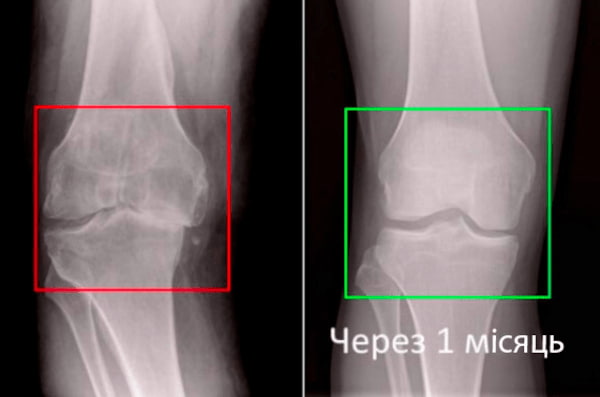

Візьміть до уваги знімок колінного суглоба 63-річного пацієнта за 1 місяць користування Artronil - суглоб повністю регенерувався.